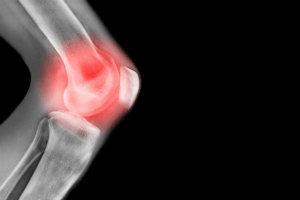

A patela tem ligamentos e tendões que a prendem no lugar. Se ela for atingida com uma força poderosa, pode se afastar de sua posição normal. Esse deslizamento é chamado de luxação e, quando isso ocorre, a patela desliza para o lado da articulação do joelho. Trata-se de uma lesão muito mais comum do que pensávamos e, com isso, as pessoas tendem a se questionar sobre o tempo de recuperação da luxação patelar.

A maioria das pessoas que sofrem com a luxação da patela descobre que ela não está mais fora do lugar. Isso ocorre porque ela volta de forma rápida e espontaneamente. No entanto, se você notar que o seu joelho parece diferente ou estranho, então ela ainda está deslocada.

Nestes casos, o tratamento inicial para uma luxação da patela é reduzi-la. Contudo, é importante que a manobra de redução seja feita por um médico e, quanto mais cedo, melhor. Assim que o osso estiver no lugar, você precisará de alguns exames para garantir que não haja fraturas.